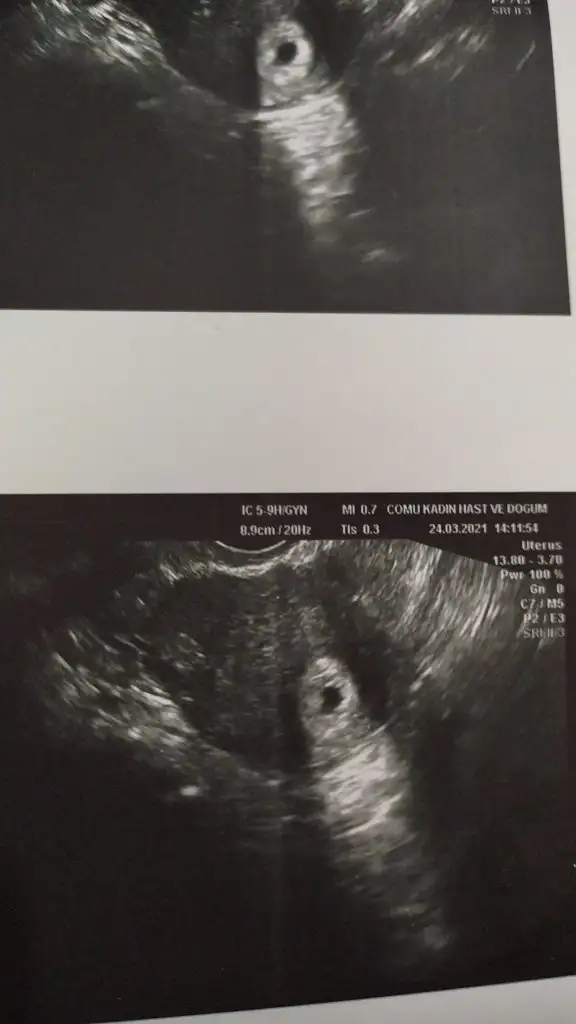

Benim içinde tahminde bulunabilir misiniz acaba vajinal ultrason görüntüsü

• IMG-20210325-WA0002.webp

• IMG-20210324-WA0001.webp